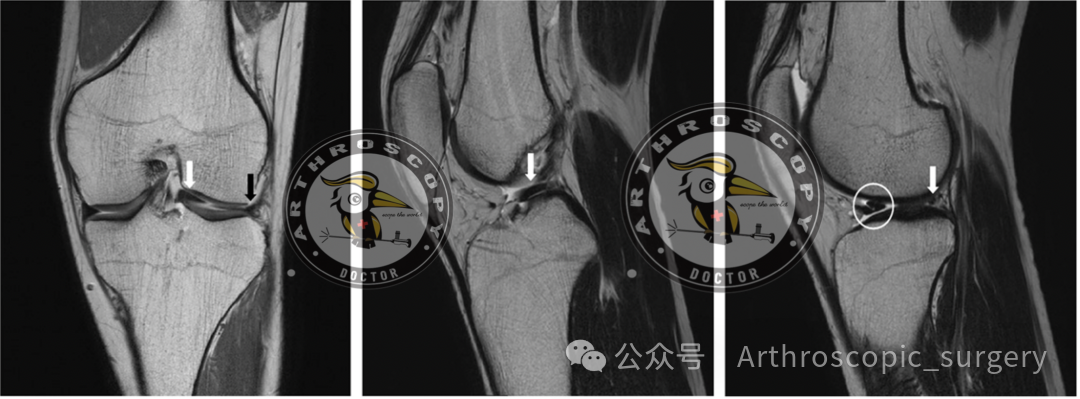

经典征象

MRI是诊断桶柄样撕裂的“金标准”,其敏感度可达90%左右。为了精准诊断这种损伤,在矢状面和冠状面总结了许多经典征象:

髁间窝片段征

Fragment within the intercondylar notch

移位的半月板碎片出现在髁间窝内。

领结征消失

Absent bow tie sign

正常半月板在矢状面上应能看到两个连续的“领结”形状,若只剩一个或消失,则提示撕裂移位。

双后交叉韧带征

Double PCL sign

移位的碎片位于后交叉韧带(PCL)的前下方,与其平行,形成“双PCL”的假象。

双前角征

Double anterior horn sign

碎片移位到前角后方,使前角看起来变成了“双份”。

翻转半月板征

Flipped meniscus sign

表现为一个异常大的前角(>6mm)。